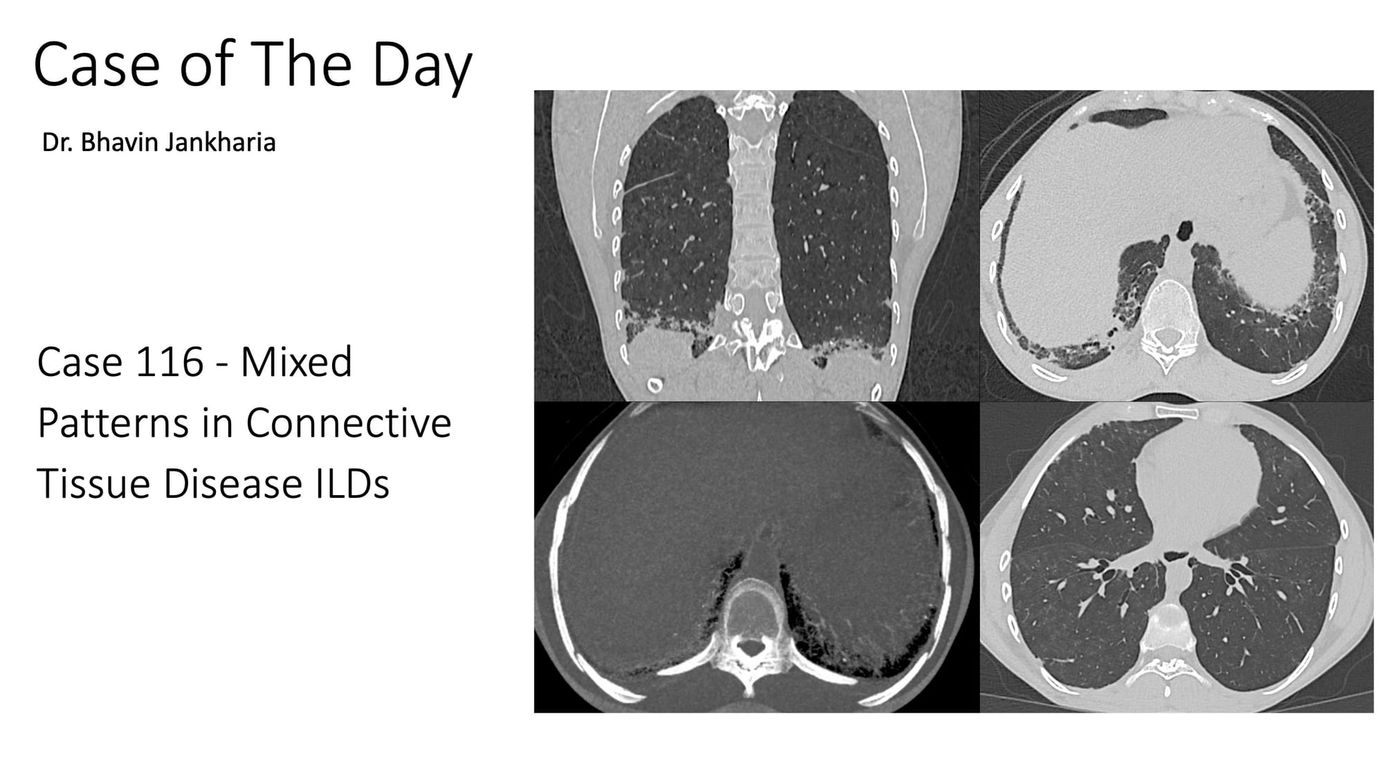

Case of the Day 116 - Mixed Patterns in Connective Tissue Disease ILDs Members Public

Mixed patterns are increasingly being recognized in CTD ILDs and should be mentioned in the report.